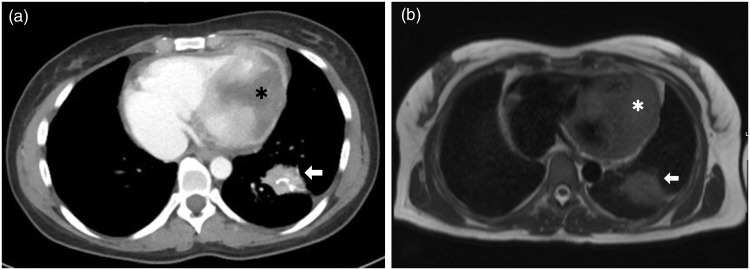

我们报告一例33岁的妇女因呼吸困难和发烧而紧急入院。病史包括完全缓解的宫颈鳞状细胞癌。胸部增强计算机断层扫描(CT)显示浸润性心脏肿块,表明可以排除肺炎。通过超声心动图和心脏磁共振成像(MRI)进一步评估肿瘤显示经壁浸润的顶室间隔,肿块延伸到左、右心室腔。这个肿块高度怀疑是心脏转移。宫颈癌引起的心脏转移极为罕见。复发的宫颈癌累及心脏应考虑,即使在治疗方法。无创成像在心脏肿块的检查中起着至关重要的作用。超声心动图、CT和MRI是心脏内病变完整检查的互补成像方式。

We report a case of a 33-year-old woman with emergency admission due to dyspnoea and fever. History included squamous cell carcinoma of the cervix in complete remission. Contrast-enhanced computed tomography (CT) scanning of the chest, which was indicated to rule out pneumonia, revealed an infiltrative cardiac mass. Further assessment of the tumour by echocardiography and cardiac magnetic resonance imaging (MRI) showed transmural infiltration of the apical interventricular septum with a mass extending into the left and right ventricle cavities. The mass was highly suspicious for a cardiac metastasis. Cardiac metastases from cervical cancer are extremely rare. Recurrence of cervical carcinoma involving the heart should be considered even after a curative therapy approach. Non-invasive imaging plays a paramount role in investigating cardiac masses. Echocardiography, CT and MRI are complementary imaging modalities for complete work-up of intracardiac lesions.